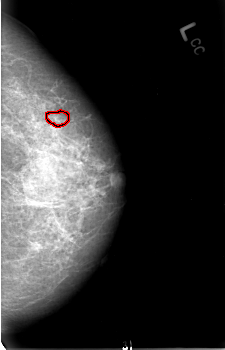

B_3007_1.LEFT_CC

LEFT_CC LINES 4544 PIXELS_PER_LINE 2920 BITS_PER_PIXEL 12 RESOLUTION 50 OVERLAY

FILE: B_3007_1.LEFT_CC.OVERLAY

TOTAL_ABNORMALITIES 1

ABNORMALITY 1

LESION_TYPE CALCIFICATION TYPE PLEOMORPHIC DISTRIBUTION CLUSTERED

ASSESSMENT 4

SUBTLETY 3

PATHOLOGY MALIGNANT

TOTAL_OUTLINES 1

BOUNDARY